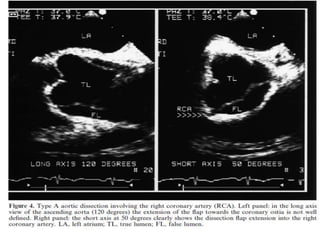

TEE AND ACUTE AORTIC

SYNDROME

Aortic dissection is a clinical emergency that is challenging to

diagnose.

TEE and CT angiography are the two most commonly employed imaging

modalities for aortic dissection.

Multiple studies have demonstrated the high sensitivity and specificity

of both modalities for diagnosing type A dissections.

The sensitivity and specificity of TEE have been reported as 90% to

100% and 94% respectively .

TEE offers the additional advantage of assessing for complications of

dissection including pericardial effusion, aortic insufficiency, and

regional LV wall motion abnormalities that suggest coronary

involvement.

One limitation of TEE is the inability to image the distal portion of the

ascending aorta and the proximal transverse aorta due to interposition

of the tracheal air column.